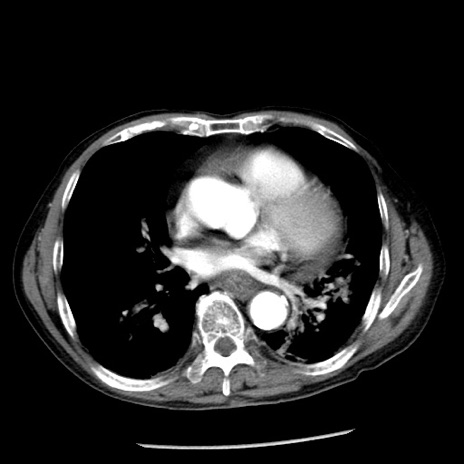

症例26(横断像)

【症例】80歳代男性

【主訴】嘔吐

【現病歴】昨晩2回嘔吐あり、今朝になっても嘔吐あり。来院。

【既往歴】胃潰瘍

【身体所見】意識清明、BT 37.6℃、BP 166/95mmHg、HR 100bpm、SpO2 97%、腹部:平坦・軟、腸蠕動音聴取良好、圧痛なし。

【データ】WBC 21900、CRP 1.46